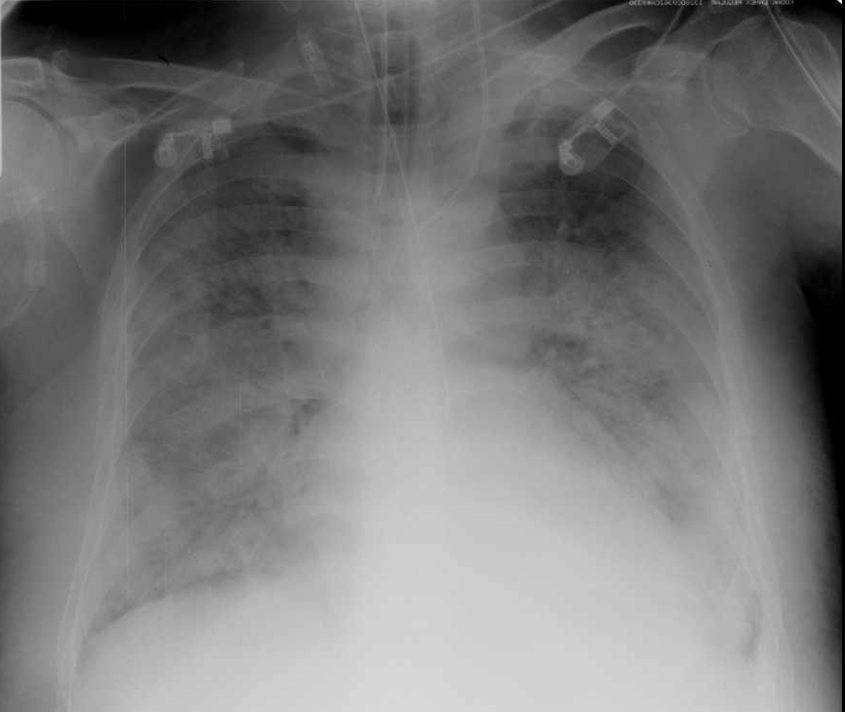

14. Typical appearance of ARDS on chest X-ray: massive, bilateral consolidations with aerobronchograms.